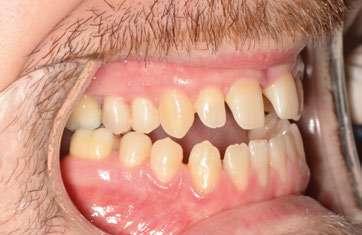

2. Análisis intraoral (Ilustración 2 y 3):

 Clase III molar y canina de Angle bilateral.

 Mordida abierta anterior > 3 mm.

 Compresión maxilar junto con mordida cruzada posterior bilateral.

 Línea media inferior desviada 2 mm hacia la derecha.

Ilustración 3. Modelos iniciales de estudio.